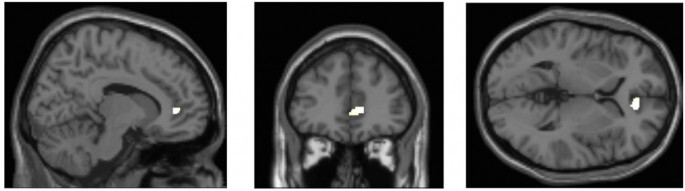

멀티태스커들의 뇌와 그렇지 않은 사람들의 뇌를 MRI로 스캔하여 살펴본 결과,

멀티태스킹이 일상화가 되면 뇌에서 감정과 공감능력 같은 사고에 관련된 부분을 담당하는

전대상 피질(anterior cingulate cortex)의 밀도가 다른 사람들보다 낮다고 합니다.